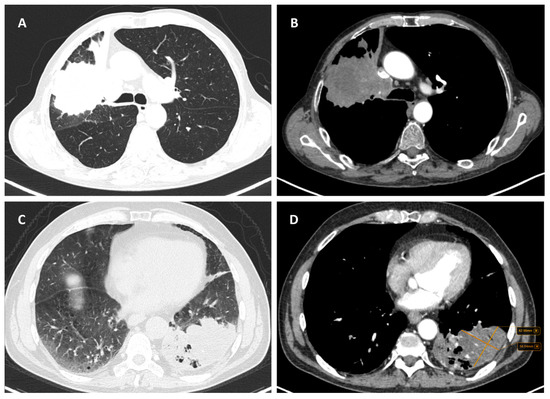

健康・医学 high-resolution CT of the lung High-Resolution CT of the Lungs | AJRの詳細情報

High-Resolution CT of the Lungs | AJR。High resolution CT scan of the chest showing the lung。CT Imaging Patterns in Major Histological Types of Lung Cancer。high-resolution CT of the lung2014-8-19W.Richard Webb, Nestor L. Muller, David P Naidichほぼ使用感なく比較的綺麗です。ごく一部書き込みがあります。Image Quality from High-Resolution CT of the Lung。本棚に置いていたので僅かな反りがあります。グレイ解剖学 第4版。健康・医学 Molecular biology。